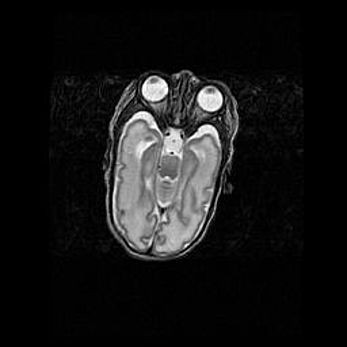

Лейкомаляция с кистозно-глиозной дегенерацией головного мозга.

Возраст: 2 месяца 25 дней

Вес: 6400 г

Окружность головы: 40 см

Срок гестации: 41 неделя

Лейкомаляцию относят к ишемически-гипоксическим повреждениям головного мозга, диагностируемым у новорожденных. При лейкомаляции в головном мозге обнаруживают очаги некроза, возникшие после тяжелой гипоксии и нарушения кровотока. В процессе морфогенеза очаги проходят три стадии: 1) развития некроза, 2) резорбции и 3) формирования глиозного рубца или кисты. Перивентрикулярная лейкомаляция (ПЛ) встречается примерно в 12% случаев среди новорожденных, обычно – у недоношенных детей, причем, частота ее зависит от массы, с которой младенец появился на свет. Наибольшее число малышей страдает лейкомаляцией, если масса при рождении 1500-2500 г.